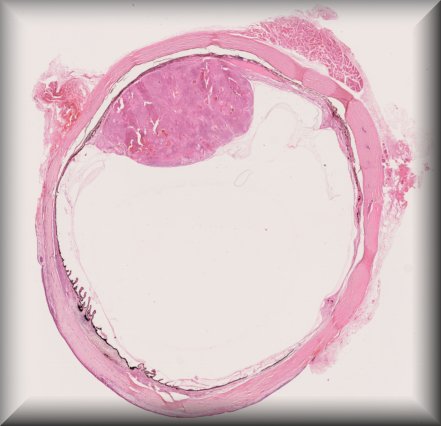

Martina Herwig-Carl (Bonn): 57 year old woman with a blind painful eye and history of intrvitreal bevacizumab injections, tumour biopsy and brachytherapy for uveeal melanoma followed by several proceedures for high intraocular pressure resulting finally in enucleation. |